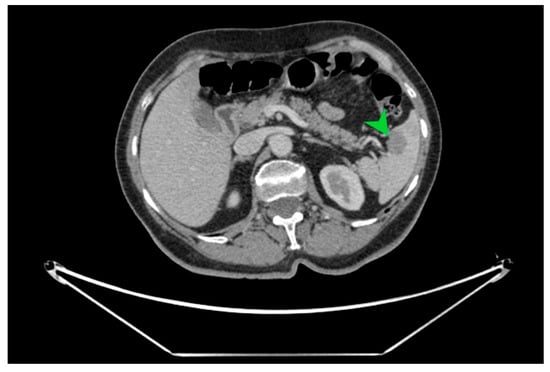

Figure 2.

CT image in cross-section on which the well-defined hypodense splenic tumor formation of 23.5/16 mm is indicated with a green arrow, with a high suspicion of splenic metastasis.

The macroscopic examination of the gastric resection specimen revealed a tumor ulceration of 3/2.5 cm (Figure 1a). Microscopic evaluation confirmed the presence of moderately differentiated intestinal-type gastric adenocarcinoma (G2), infiltrative in the subserosa, with vascular tumor emboli present (Figure 1b). Twenty-eight lymph nodes were identified, and tumor invasion was confirmed in five of them. The surgical resection margins were free of tumor invasion. Postoperatively, the patient remained under oncological follow-up, and approximately 10 months postoperatively, he reported significant weight loss and physical asthenia, symptoms that were initially considered to be associated with the complex treatment of the neoplastic disease. However, serum determination showed a slight increase in CEA to 6.5 ng/mL from 3.2 ng/mL and an increase in CA19-9 to 160 U/mL from 21 U/mL (Table 1), which led to the decision to perform an abdominal CT that revealed the presence of a hypodense, poorly iodophilic splenic lesion, measuring 23.5/16 mm, raising suspicion of a splenic metachronous metastasis (Figure 2). The imaging examination was continued with a PET-CT scan, which highlighted the pathological uptake of 18F-2-deoxy-2-fluoro-glucose (18F-FDG) at the level of the previously described lesions without detecting other areas of suspected metabolic hyperactivity (Figure 3).